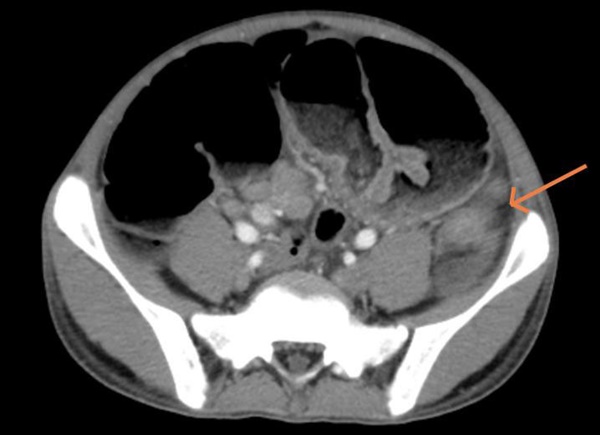

Hình ảnh chụp cắt lớp vi tính ổ bụng cho thấy, các quai ruột non và khung đại tràng của bệnh nhân giãn lớn, đường kính lớn nhất 57mm. Bệnh nhân được chẩn đoán tắc ruột/theo dõi ung thư đại tràng trái và chỉ định mổ cấp cứu làm hậu môn nhân tạo đại tràng trái.

Hình ảnh cắt lớp vi tính ổ bụng của bệnh nhân